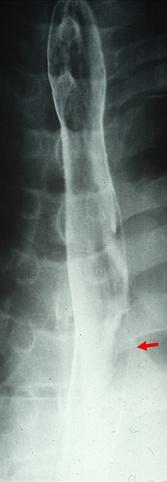

疾患(病理主体)の分類悪性上皮性腫瘍/扁平上皮癌

部位(臓器別)食道/中

検査方法X-P

腫瘍の肉眼分類0型(表在型)/I型(Isp)

病変の最大径(ミリ)15〜19

腫瘍の深達度sm